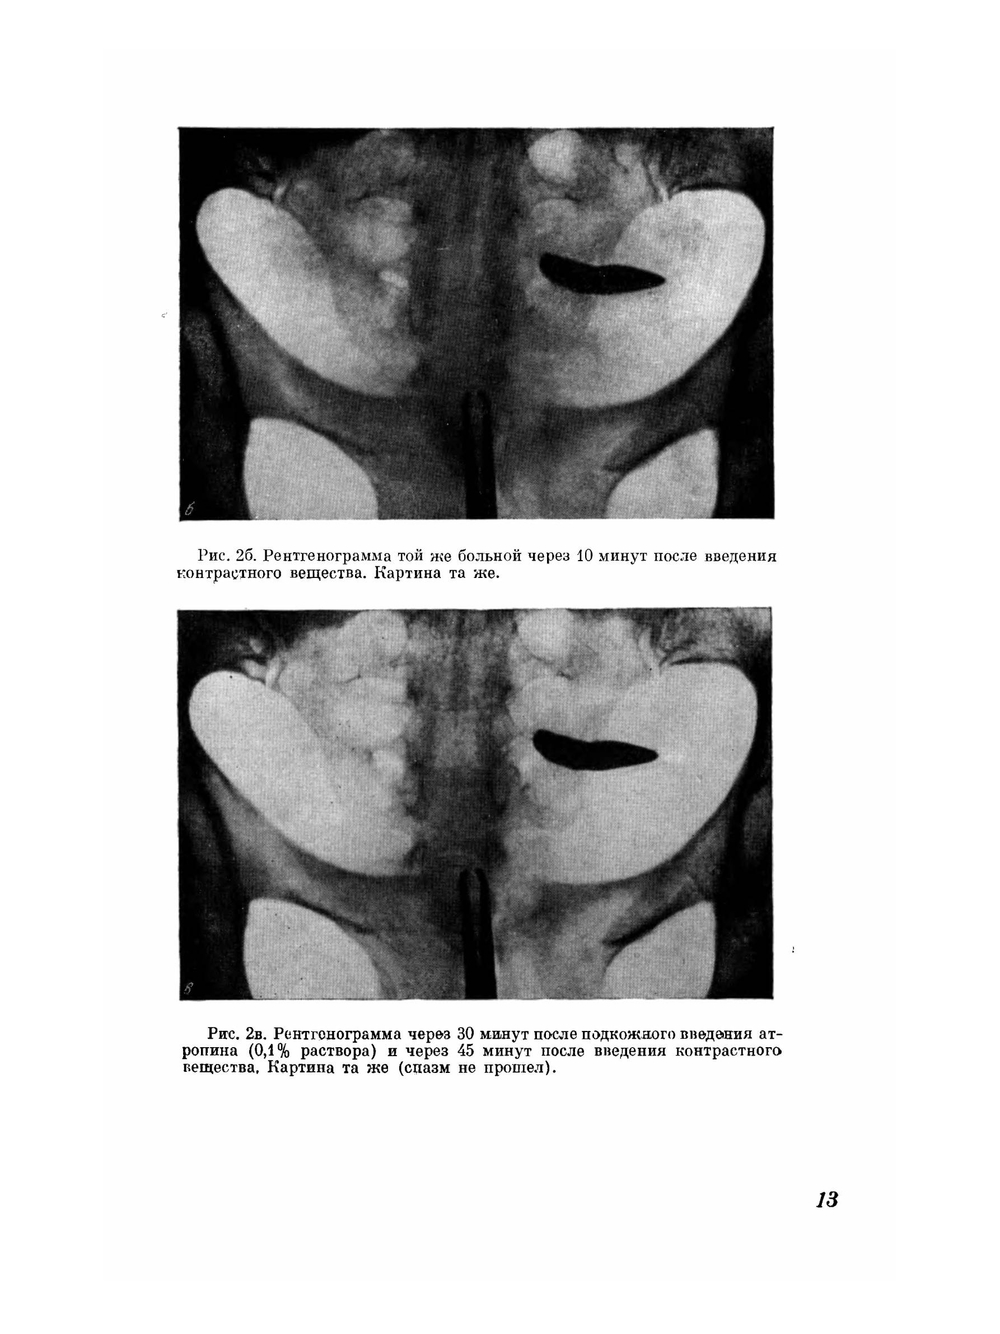

Рентгенологическая диагностика патологических изменений женских подовых органов с помощью контрастной гистеросальпингографии все шире и шире находит практическое применение, она помогает поставить правильный диагноз и применить целесообразный метод лечения. Многие врачи-гинекологи вследствие неумения читать рентгенограммы предоставляют их на интерпретацию рентгенологам общего профиля, которые дают заключение без достаточных знаний гинекологии, не учитывая особенности условий и техники проведения гистеросальпингографии. Гистеросальпингографии является объективным и документальным методом в оценке проходимости или непроходимости труб. В этом заключается одно из преимуществ его перед продуванием последних. Гистеросальпингография дает четкие контуры слизистой матки и труб и дефекты наполнения их полостей, на основании которых можно установить тот или иной диагноз (туберкулезный эндометрит, эндометриоз, полипы, миомы и т. д.). Желание помочь практическому врачу в проведении гистеросальпингографии и дать возможность разобраться в многообразных рентгенологических картинах привело нас к мысли поделиться своим опытом и выпустить альбом, в котором помещено около 150 рентгенограмм, размещенных по разделам соответственно тематики. Считаем, что подготовка кадров акушеров-гинекологов, владеющих не только правильной техникой гистеросальпингографии, но и умением хорошо разбираться в каждой рентгенограмме, обеспечит наиболее правильную диагностику и своевременное применение рациональной терапии.